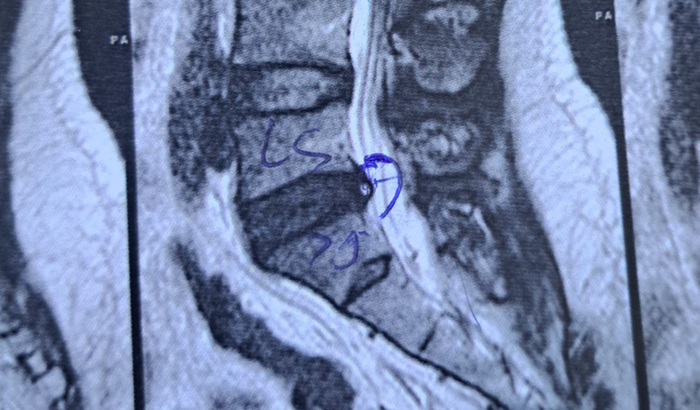

Eu sou Allen Rodrigues sou dançarino e criador de conteúdo. Trabalho em uma fábrica de peças para automóveis na qual lesionei a vértebra L5,S1. Estourando o disco da coluna, minha cirurgia está pra ser marcada já, porém tenho filhos e minha perícia no INSS foi marcada pra dia 4 de dezembro, não terei condições nem de dar o sustento a eles e nem de pagar a anestesia da minha operação. Peço a ajuda de vcs pra conseguir manter minha família nesse período difícil e poder voltar logo a dançar que é oque me traz felicidade. Conto o bom coração de vocês . OBRIGADO ❤️